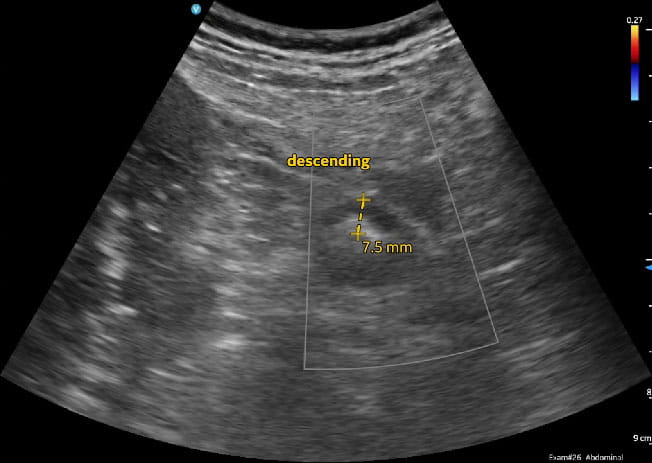

“The use of ultrasound in patients with IBD is fairly new in the U.S.,” Dr. Nguyen says. “In the past, we have only used ultrasound to look at the gallbladder and the liver, not the intestine or the colon. Now, we are using it in patients with IBD to look for signs of inflammation, to manage treatment and to diagnose other gastrointestinal complications such as diverticulitis, bowel obstruction and appendicitis.”

In addition to diagnosing IBD and other GI conditions, intestinal ultrasound can be used post-surgery to proactively identify potential complications, such as pockets of infection, he adds. Studies have shown that ultrasound is accurate in diagnosing IBD and monitoring response to treatment.